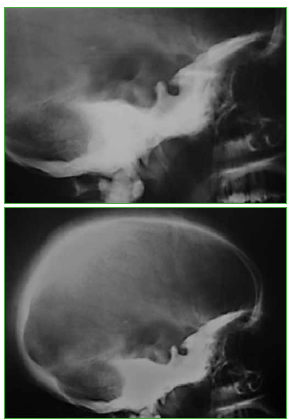

Figura 3.

Radiografías de cráneo de perfil que muestran hiperdensidad de los huesos de la base del cráneo.

Se sospecha osteopetrosis al intentar la osteosíntesis de fémur, que resulta infructuosa debido a la extrema dureza de la cortical. Asimismo, se detecta estrechamiento del canal medular de los huesos largos con incremento de la densidad y el espesor de las corticales (Figura 2) y, en las radiografías de cráneo (Figura 3), hiperdensidad de los huesos de la base que, en conjunto con las muestras de anatomía patológica tomadas durante la cirugía de fémur, confirman el diagnóstico de osteopetrosis. Se la trata con un yeso conformado en el húmero hasta la consolidación radiográfica a los tres meses (Figuras 4 y 5). Los controles radiográficos se realizaron a la semana y a los 1, 3, 6, 9 y 12 meses. El puntaje de la UCLA para hombro fue de 30, un resultado excelente. En cuanto al puntaje de la Clínica Mayo de codo fue de 100, para el que se evidenció solo la pérdida de 5º de extensión.